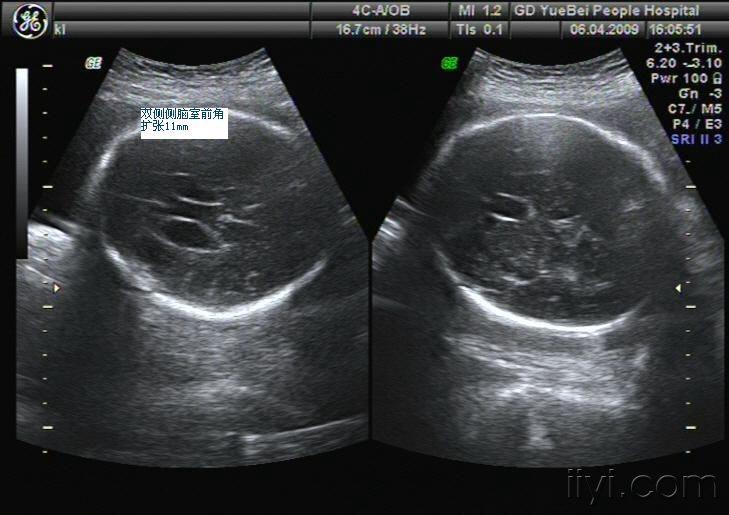

胎儿脑积水一例

胎儿脑积水

谁发一张4或5或6个月的胎儿脑积水的b超图片